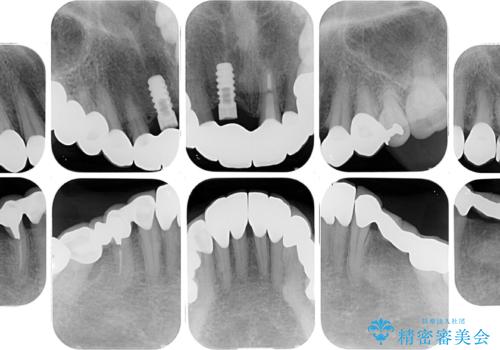

- 歯肉ラインの段差や、歯根が黒く見えている前歯を気にして来院された患者様です。

前歯のインプラントは埋入されたポジションが望ましい位置ではなく、インプラントを活用して段差を回収することは不可能と判断し、歯肉移植によりインプラントを隠して、ブリッジにて歯肉ラインを整えることとしました。

臼歯部の治療も必要と判断されましたが、前歯部を中心とした審美領域をオールセラミッククラウンによる補綴治療を行うこととしました。